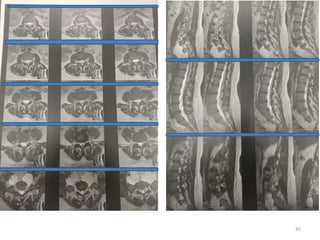

Radiologic assessment

Magnetic Resonance Neurography (MRN)

relation to surrounding structures

Extent of involvement

Radiology DD

neurofibromas

• Centrally located within the nerve sheath

• Fascicles are runnig through the tumour

• Expanding the tumour in fusiform fashion

• Commonly show a target sign, peripheral

hyperintense rimand a central hypointense

regionin T2 MRI

• Hypoechoic on ultrasound

• Their appearance mimic the ganglion cyst.

• Several fascicles involved in the tumoural

mass and they are functioning fascicles so,

intra-fascicular dissection is a must with

preservation of the fascicles.

• If fasciles can not be idnetified except the

entry and exit fascile stumps, nerve graft

cables are used for interpositional grafts or

conduits.

• Permanent neurologic dysfunction is more

common following tumours in proximal arm,

immobile, painful and > 4 cm in size

schwannomas

• Eccentric located

• More encapsulated

• Fascicles run at periphery

• show diffuse contrast

enhansed on T1 MRI

• Single fascicle enters and

exits the tumoural mass and

it is non-functioning so, you

can resect mass and cut it.